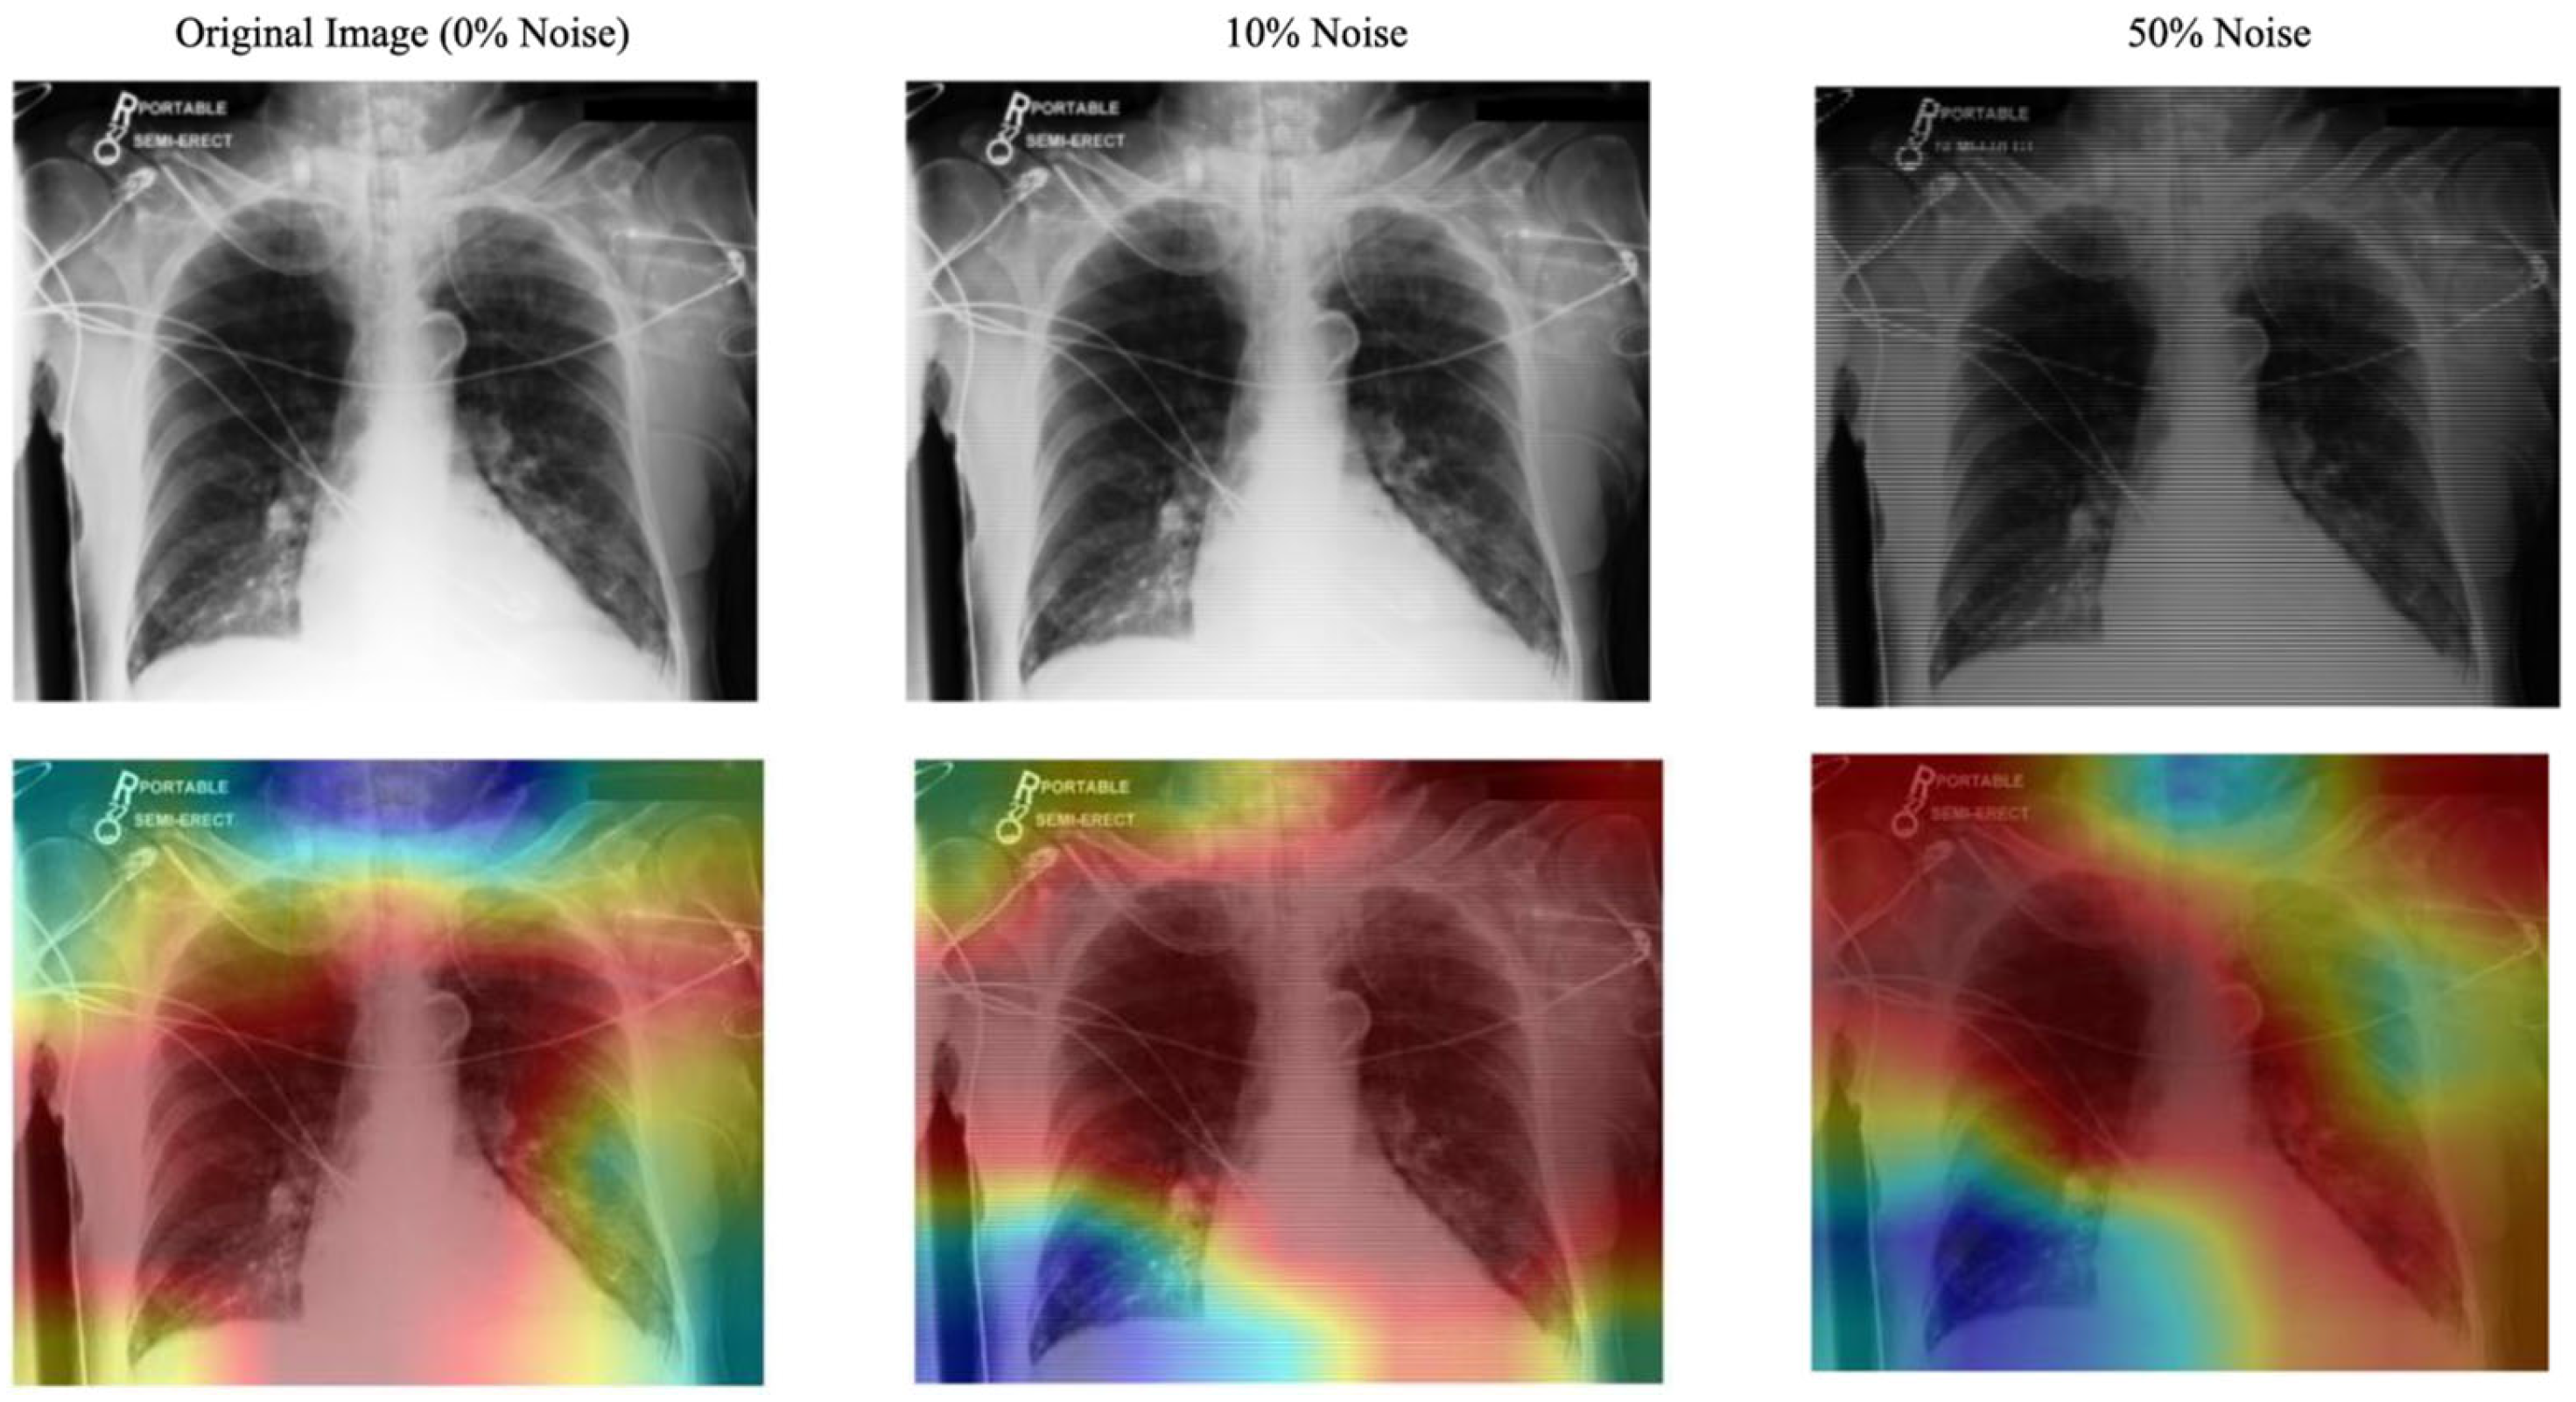

- Evaluation of the Approach. We evaluate our approach and demonstrate robust performance under noisy conditions, showing resilience to misaligned fixation maps. We further assess the interpretability of the model by utilizing Grad-CAM, ensuring that the generated visual explanations align with expert-annotated ROIs. This alignment enhances the clinical reliability of the model’s predictions.

| Noise Level (%) | CXR AUC | CXR+ Fixation Map AUC (No Shared Params) |

|---|---|---|

| 0 | 81.41 | 83.30 |

| 10 | 80.28 | 81.08 |

| 50 | 74.61 | 75.86 |